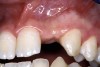

Periapical radiographs were taken to help determine the mesial-distal inclinations of the adjacent tooth roots (Figure 1). The radiographs revealed a serious issue, convergent roots for the right canine and right central, which eliminated that area as a potential implant-receptor site. The space between the left central and canine teeth was minimal, although the roots were relatively parallel. Clinical examination (manual palpation of the root eminences superiorly to the vestibule on the right side) confirmed the root convergence (Figure 2A). The flat, wide zone of the keratinized tissue and lack of interdental papilla was evident for the missing right lateral incisor. There was a marked difference in clinical appearance for the left lateral, which could impact the eventual plan of treatment (Figure 2B). Other significant clinical findings included bilateral facial bone concavities, which existed as a result of the congenitally missing tooth roots. As a diagnostic cue to the underlying bone topography, it is important to follow the demarcation between attached and unattached gingival tissue, and note the crestal width of the available keratinized tissue (Figure 2C).

Figure 2a  Pretreatment buccal views showed (A) root convergence, (B) a difference in clinical appearance of the left lateral, and (C) significant crestal width of keratinized tissue.

Figure 2a

Figure 2b  Pretreatment buccal views showed (A) root convergence, (B) a difference in clinical appearance of the left lateral, and (C) significant crestal width of keratinized tissue.

Figure 2b

Figure 2c  Pretreatment buccal views showed (A) root convergence, (B) a difference in clinical appearance of the left lateral, and (C) significant crestal width of keratinized tissue.

Figure 2c